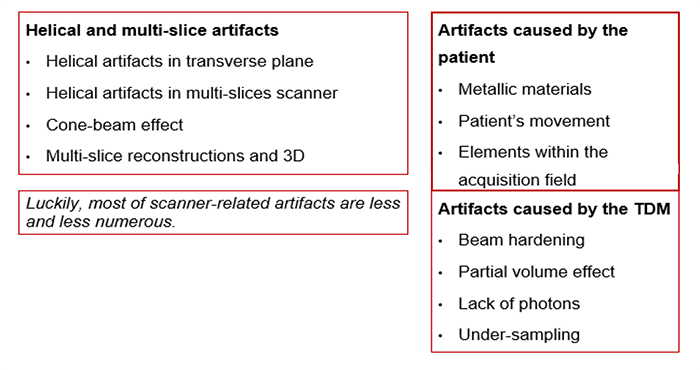

Origins of Artifacts

Artifacts are commonly encountered in clinical CT and can obscure an area of pathology making it impossible for a radiologist to visualize.

There are many different types of CT artifacts including noise, beam hardening, scatter motion, helical, cone-beam and metal artifacts.

Helical Artifact

Helical artifacts can sometimes be seen with faster scanning techniques. In general, the same artifacts are seen in helical scanning as in sequential scanning. However, there are additional artifacts that can occur in helical scanning due to the helical interpolation and reconstruction process. The artifacts occur when anatomic structures change rapidly in the z-direction (ie, at the top of the skull) and are worse for higher pitches. Helical and multisection technique artifacts are produced by the image reconstruction process.

This set of artifacts shows a fast anatomical variation in the Z direction.

Cone-Beam Artifact

When the collimation is greater than the Z-axis, the detectors will receive less information. This distorts the image during the tube rotation. When mathematical algorithms are used the artifact can be corrected. High collimation highlights the cone-beam artifacts.